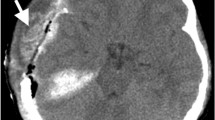

A single rater, blinded to clinical data, performed all measurements using anonymized images in random order to avoid bias. Noncontrast enhanced CT scans with a slice thickness of 4 mm were used. Muscle volume was measured between the zygomatic arch (first slice depicting the completely closed arch) and the inferior temporal line. These landmarks were chosen because the temporal muscle is located very distinctively between the cranial bones (inside) and the temporal fascia (outside) within this area. The muscle was manually marked and 3D-reconstructed afterward using the AW volume share 5 software (GE Healthcare, Chicago, IL) (Fig. 1).